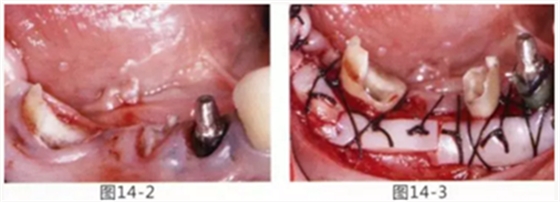

病例5

為了提高對修復(fù)體的術(shù)后效果,以生物學(xué)寬度,獲取附著齦為目的進行游離齦移植的病例

圖14-1 修復(fù)體周圍角化牙齦較少,很難進行清潔的狀態(tài),并有緣下齲壞的發(fā)生。

圖14-2,3 徹底去除齲壞后,試圖通過游離齦移植獲取生物學(xué)寬度和附著齦。

圖14-4~6修復(fù)體周圍角化牙齦較少,很難進行清潔的狀態(tài),并有緣下齲壞的發(fā)生。

圖14-7 配戴最終修復(fù)體完成5年后的狀態(tài)。保持良好。